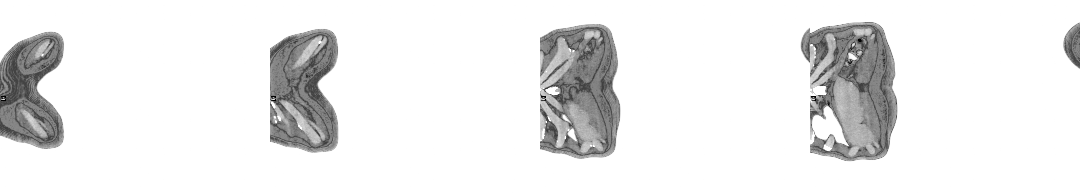

A PET scan is organised a few days later, at St Barts Hospital, in the shadow of St Paul’s. The body is flooded with a tracer radioactive fluid, after which you are locked into a lead-lined box for three-quarters of an hour to allow it to bake in. The scanner then detects where the tracer has been absorbed by cell growth anywhere in the body it is directed, producing reams of flowing light captured to film, copies of which—scans of my own body—are used throughout this post.

The moment I saw the very first scan the doctors showed me (bottom right, above: an MRI, rather than PET, as it happens)—on a small monitor wheeled into my cubicle at the Homerton—seemed to say everything at once. As I turned my head to look at the image of my brain on the monitor, I glimpsed also the tattoo on my left arm suddenly aligned with it (bottom left)—a tattoo of a bhikkhu meditating in flames, inked twenty years earlier, with the bhikkhu meditating as descibed in the Buddha’s Adittapariyaya Sutta (Fire Sermon)—such that the tattoo of the bhikkhu and the scan of the brain, aligned properly. One presaged the other by years, holding out its hand to the other. They reflected each other so neatly, with the tumour in the cerebellum showing up as the red-orange fire bursting through from within, which the bhikkhu sits through.

The wrinkled surface of the cerebral cortex in the scan echoed the Bhavachakra—the wheel of Saṃsāra, of cyclical existence (“Saṃsāra… is a Sanskrit word that means ‘wandering’ as well as ‘world’, wherein the term connotes ‘cyclic change’ or, less formally, ‘running around in circles’)10—against which the bhikkhu rests in the tattoo. Here is an image, not only of that empty time turning that we have talked of, of cyclical return and, dare I say it, reincarnation (though in this formulation, reincarnation is mere repetition, as in the ‘natural’ repetition of pagan society). In the original Fire Sermon, the argument is that the bhikkhu must free themself from the grasping tyranny of the senses. We, on the other hand, will be moving in the other direction. In any case, this combined image almost made me fall out of bed.

On seeing further scans, I recognised, eg., my rib cage as something indeed very much like the frame of Israel’s tents (above, top left), beaming on the shore of the infinite (Blake), but also, in the twisting images of the torso, I am struck by the sprawling energies at play, unleashed by disease. No longer is there the assumed underlying durable person, sealed away from the totality, cybernetically establishing their personal border by fending off and repurposing the chaos, sickness and disorder without. Instead, raw energies start to coalesce, turning Urizenic, mechanical rigidity into flashes, streaks and pulses of contending light.